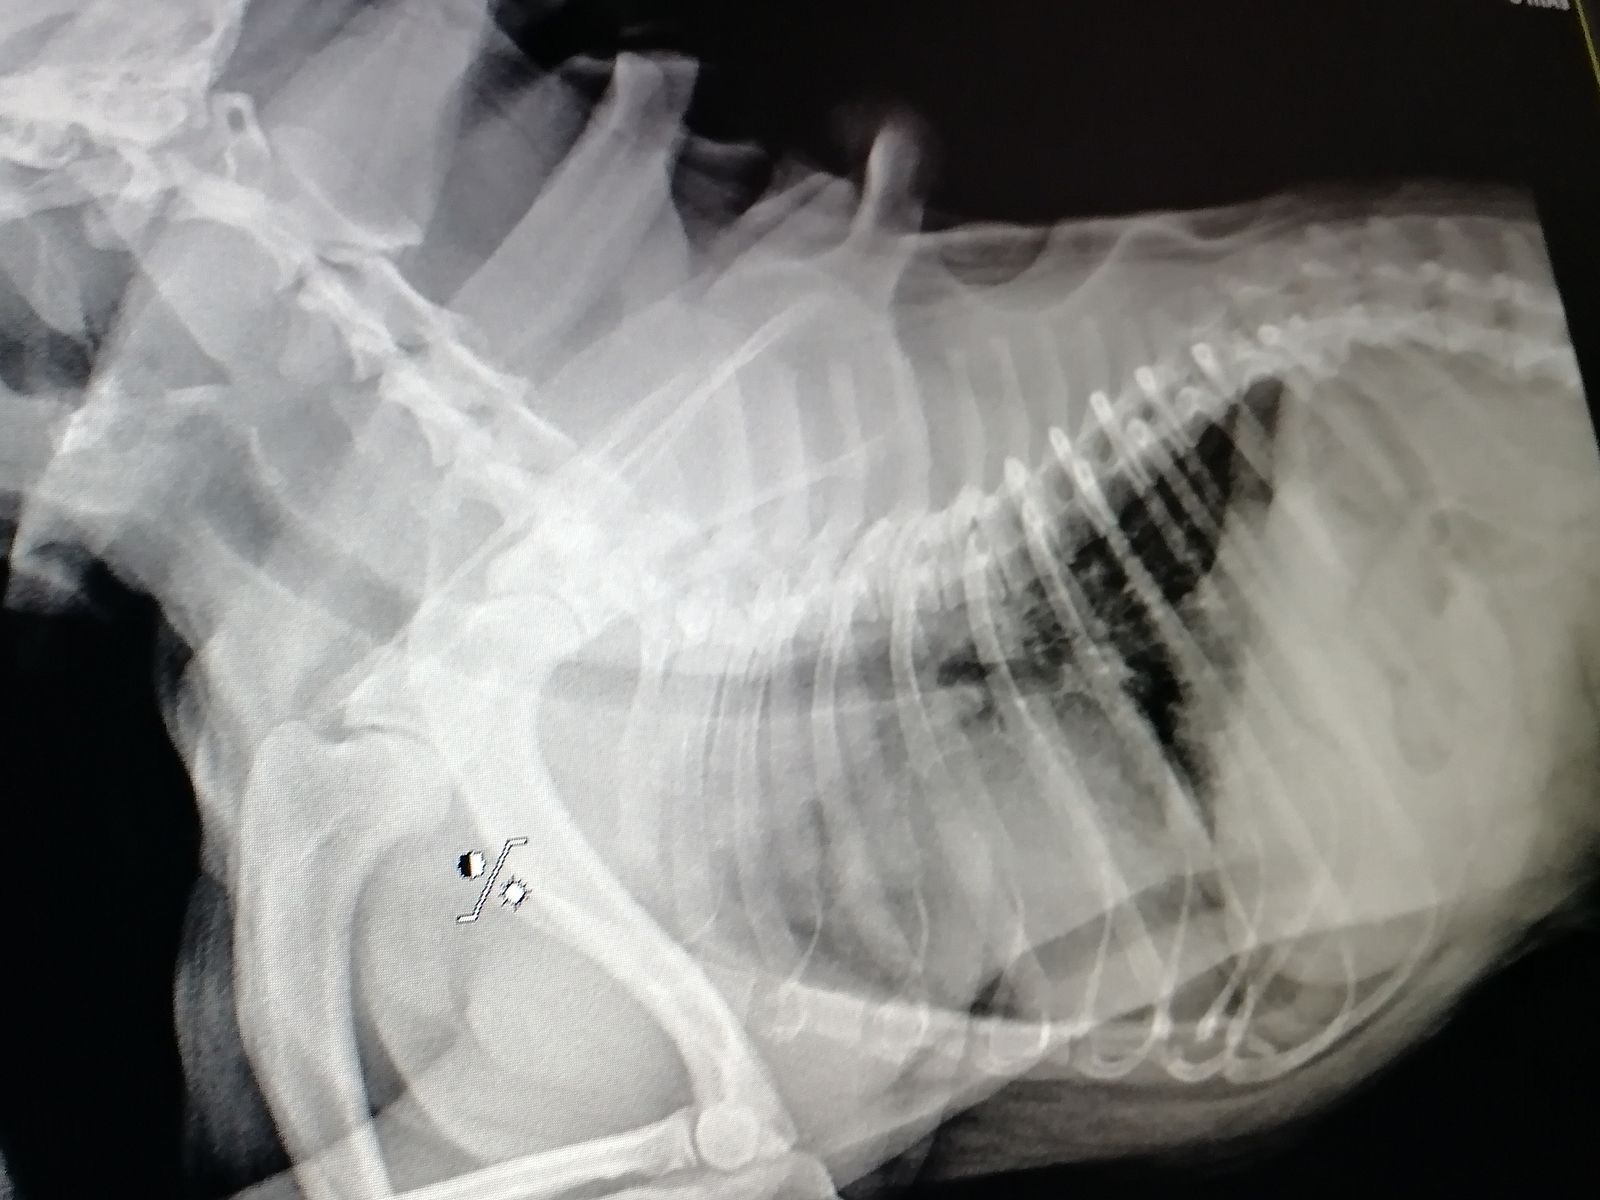

Вопрос ветеринарам по рентг. снимку собаки

Собака простужена, более 2х недель кашель. Вялый.

Подскажите, пожалуйста, на снимке Вы видете воспаление?

Сегодня сказали, что похоже на новообразование....Плачу...

цифровой в двух проэкциях